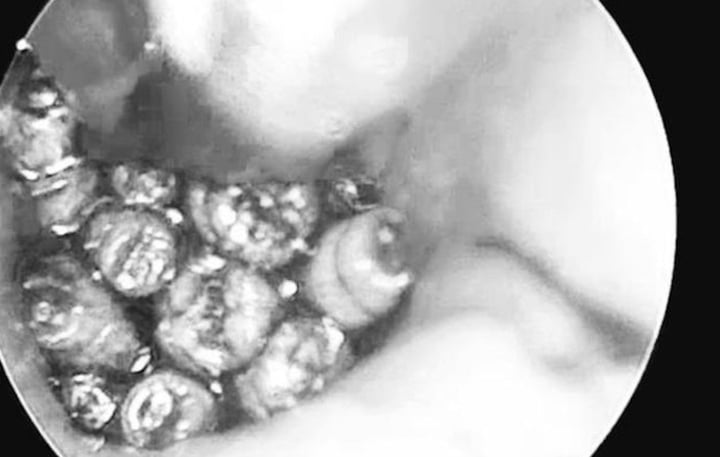

Thực hiện nội soi, các bác sĩ phát hiện hàng chục con giòi đang sống trong tai người bệnh. (Ảnh: BVCC)

Trước đó, lúc 14h ngày 4/5, khoa Tai Mũi Họng, Bênh viện Đa khoa tỉnh Quảng Trị tiếp nhận bệnh nhân H. nhập viện cấp cứu trong tình trạng đau tai trái dữ dội, ù tai, nghe kém kèm chảy máu tai lượng nhiều. Thực hiện nội soi, các bác sĩ phát hiện ống tai hẹp, đọng nhiều máu tươi. Khi hút sạch máu, quan sát thấy dị vật màu trắng di động, nhiều hình ảnh giống con giòi lấp đầy hòm nhĩ, màng nhĩ thủng rộng.

Sau khi làm các xét nghiệm, các bác sĩ đã nội soi, gắp hàng chục con giòi sống trong tai giữa của bệnh nhân. Hiện sức khỏe bệnh nhân ổn định và tiếp tục được theo dõi tại bệnh viện.